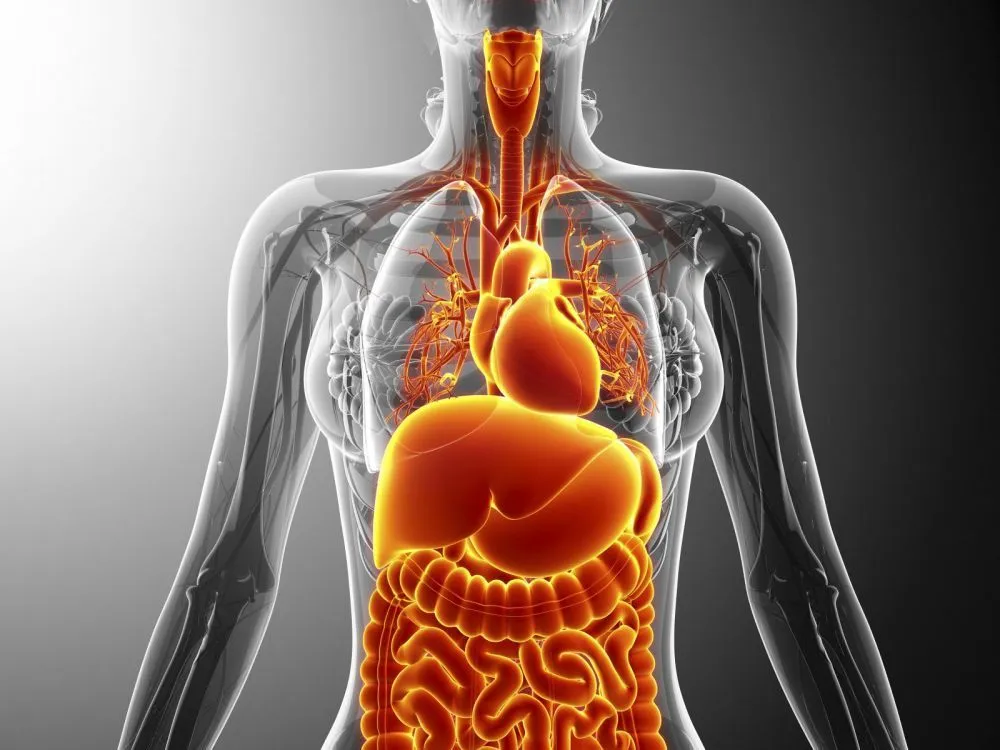

Des solutions avancées pour le diagnostic assisté, la détection précoce des pathologies et l'analyse précise d'images médicales par Intelligence Artificielle.

Prediction de priorité d'organes

Notre intelligence artificielle révolutionne l'allocation de priorité et de classification des organes grâce à des algorithmes prédictifs avancés.

- Réduction critique du temps d'attente pour les patients

- Augmentation significative des greffes réussies

- Taux de réussite améliorés